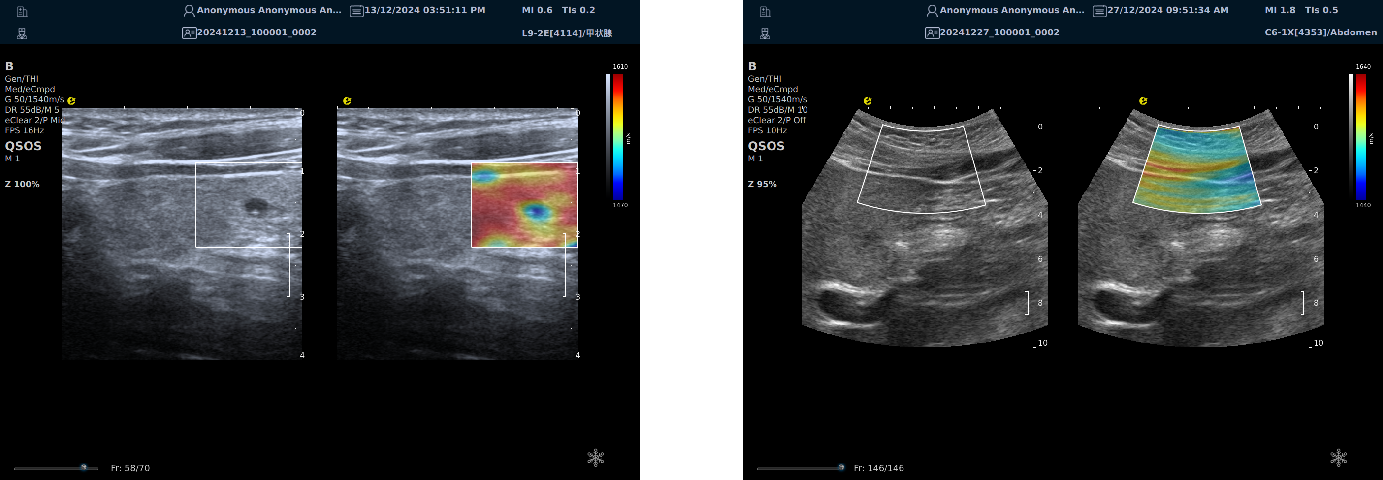

实时剪切波弹性成像

评估组织的软硬,并且提供定量数值,从而提示组织的良恶性。

image.png

鉴别诊断、精准分级、定量评价、穿刺引导、疗效评估、随访观察

恶性占位常常向周边组织进行侵润及扩散,二维很难观察到浸润部分的边界。使用实时剪切波成像能够对占位及周边组织进行硬度评估,通过颜色编码来区分不同组织的硬度信息,直观的观察占位组织的边界信息,更方便区分占位组织和正常组织的边界,准确评估消融范围。

左图病例所示:

钼靶阴性,B型发现非肿块病变

剪切波弹性成像见明确的硬度增高区域。

穿刺及手术病理结果:浸润性导管癌(IDC)

非肿块型病变:B型图像无法确认病变范围,E成像帮助发现异常区域和评估